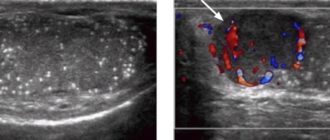

Микрокальцинаты в яичках у мальчиков Направление на УЗИ мошонки врач выдает пациенту при наличии